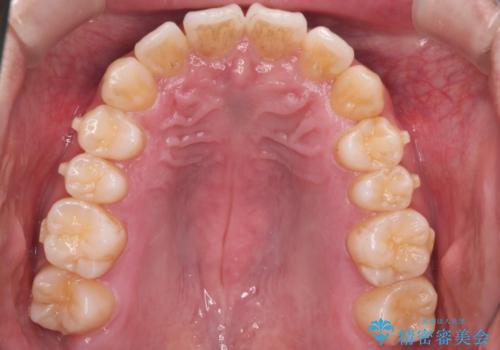

- 上の歯が出ているのが気になるのを主訴にご来院されました。人前で話すお仕事をされており目立たないマウスピース治療を希望されていました。

口元のEラインは気にならないとのことだったのでインビザラインにて治療していくことにしました。

IPR(歯と歯の間を削る処置)と歯列拡大をすることで前歯を少し下げ、がたつきを改善していく治療計画を立てました。

上の前歯が出ているという主訴が綺麗に改善されました。

その他の部位のがたつき、奥歯の噛み合わせも以前と比べると良くなっています。